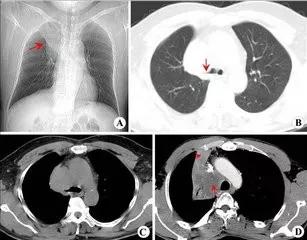

(4)CT检查

和以往的胸部X线检查相比,肺部所有的区域都能够正确的检查。是否向淋巴结转移等也能做出正确的判断。对于检查是否患有肺癌以及进行到什么程度等都是十分重要的检查手段之一。

最近开发出来的螺旋式CT能够检查出非常小的病变,对于身体检查和精密检查发挥着很大的威力。

李先生,70岁,2016年4月确诊为左肺腺癌Ⅳ期,5月开始实施化疗共计6次,2017年复查,肺部病灶较前进展,再次化疗一周期后拒绝再次化疗,转为NK细胞免疫治疗。

2017年6月至2019年12月行NK细胞免疫治疗共计6次。

治疗获益:2017年胸部CT显示肿块大小为42*27*30(mm)、40*24*36(mm),2018年复查,病灶略缩小,大小为30*31*27(mm)、35*25*29(mm)。患者临床症状较前得到极大改善,精神、饮食、体重均恢复至病前水平,病情平稳。